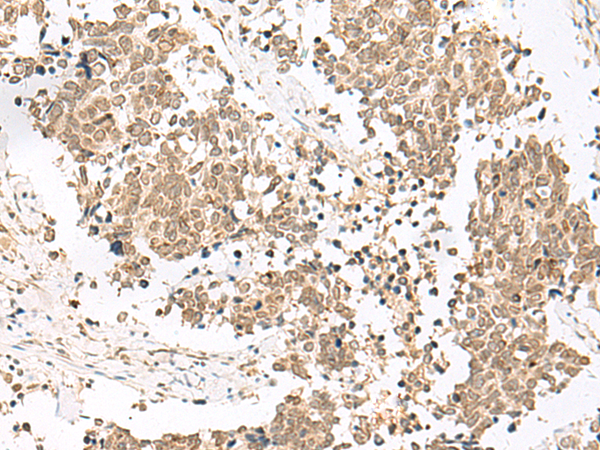

IHC positive control:

Human lung cancer and Human esophagus cancer

IHC Recommend dilution:

40-200